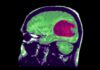

Virüsün Alzheimer riskini artırabileceği düşünülüyor çünkü virüs parçaları ömür boyu vücudunuzda kalıyor ve beyne giderek Alzheimer’ın ayırt edici özellikleri olan amiloid-beta plakları ve tau oluşumunu tetiklediklerine dair bazı kanıtlar var.

Alzheimer veya demans geliştiren katılımcıların yaklaşık yüzde 89’unda herpes simpleks virüsü bulunurken, bilişsel bozukluğu olmayanların yüzde 82’sinde virüs vardı.

Araştırmacılar, virüse sahip olmanın demans riskini iki katına çıkardığını belirledi.